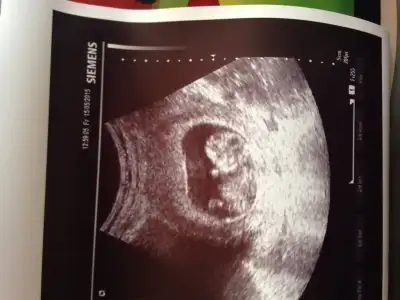

sağol canım ağzına sağlıkCanım seninkini erkek bebeğe benzettim ikinci Fotoğrafın alt kısmında bir şeyler var gibi. Ama bebek arkasını dönmüş bu teori için yandan ya da önden olması lazım Fotoğrafın.

Canım nub teorisi için 12-13 haftalar en ideal haftalar. Kese teorisine koy istersen ama bence o teori nub teorisi gibi bilimsel değil.

Tamam canım inşAllah. Ikili teste gittiğinde Bebeğin yandan fotoğrafını iste. O hafta en uygun zaman.Cevabin için tesekkur ederim canım kismet olursa 4 hafta sonra koyarım o zmn yorumlarsin insallah

ben nub göremedim. yani anlamadım fotodan